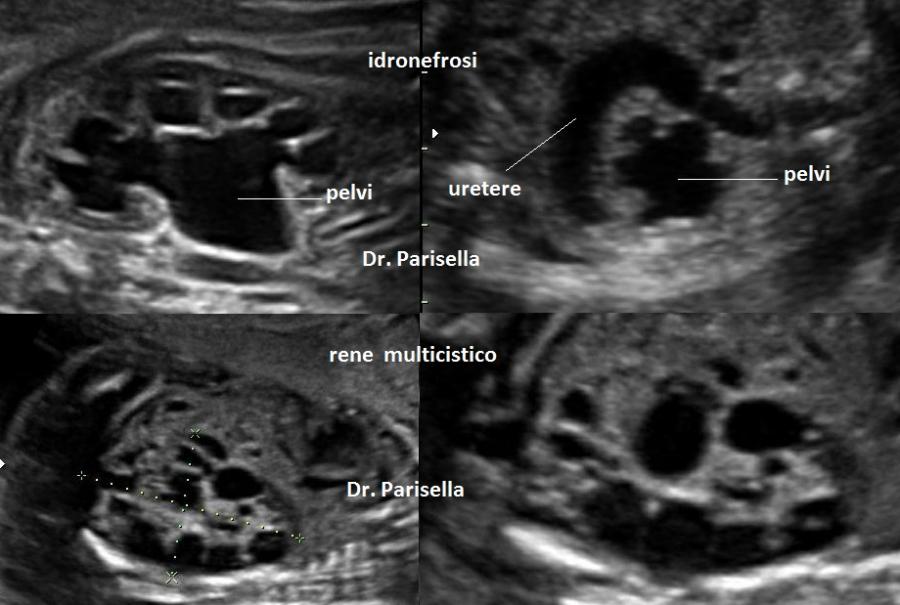

Possono essere associate cardiopatia congenita (Tetralogia di Fallot), anomalie renali e dismorfismi come micrognazia ed orecchie basse. Possono essere presenti altre anomalie scheletriche come ipoplasia omero, ulna e femore, piede torto (equino-varo), displasia congenita dell'anca.